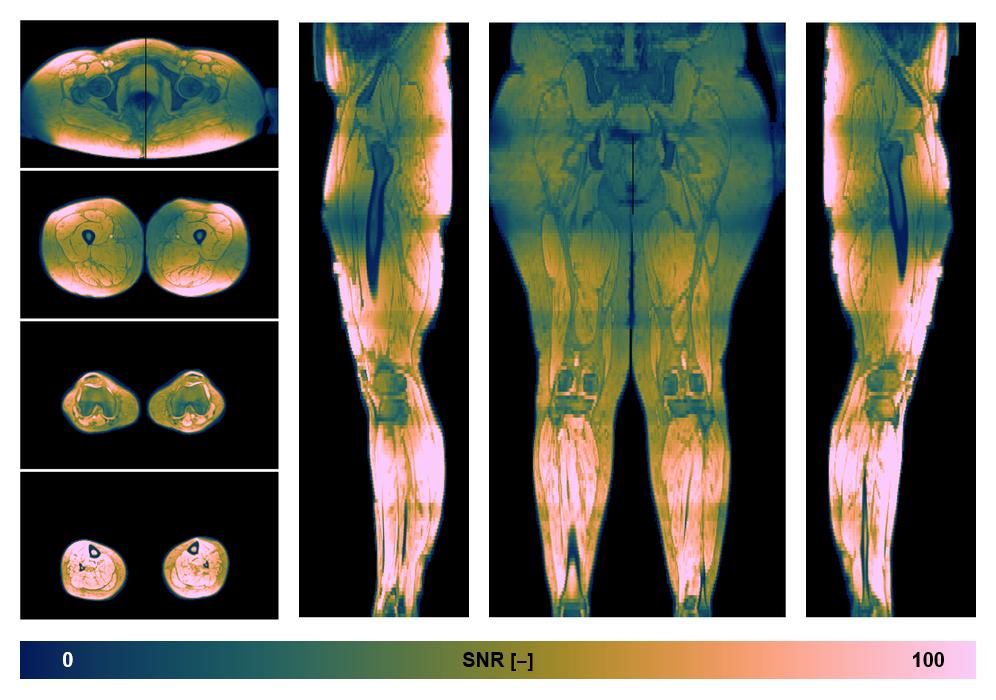

• SNR distribution

The SNR distribution of the dixon data.